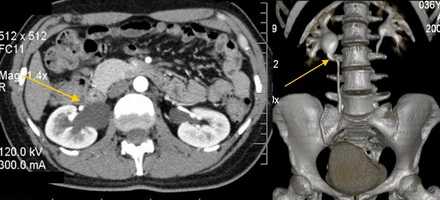

КТ

Мультиспиральная компьютерная томография. 3D реконструкция. Стеноз лоханочно-мочеточникового сегмента, гидронефроз справа.

Исследование неинвазивно и с высокой точностью показывает структурные изменения мочеполовой системы. На основании снимков проводится трехмерная реконструкция, что позволяет увидеть объем поражения и протяженность деформированного участка мочеточника. Не отражает функциональных изменений.